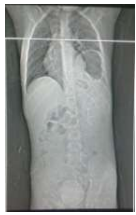

RN em sala de parto apresentou desconforto respiratório e foi encaminhado para UTI neonatal. Na admissão apresentava desconforto respiratório, cianose discreta e SO2 90%. Fez RX de tórax com o seguinte achado radiológico: Enunciado 4043979-1

Diante deste achado, assinale a alternativa que indica o diagnóstico e a melhor conduta.